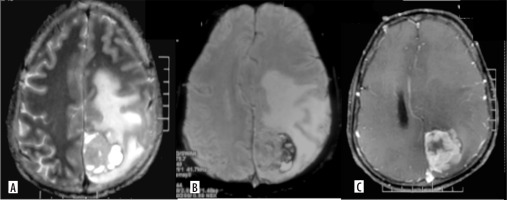

Figure 3

Gliosarcoma. Axial T2 (A) shows a cortical-based solid cystic surface-based mass in the left parietal lobe with significant perilesional edema. On axial GRE (B) the lesion shows peripheral blooming suggesting hemorrhage. On axial (C) post-contrast image, the lesion shows intense nodular enhancement and central necrotic areas